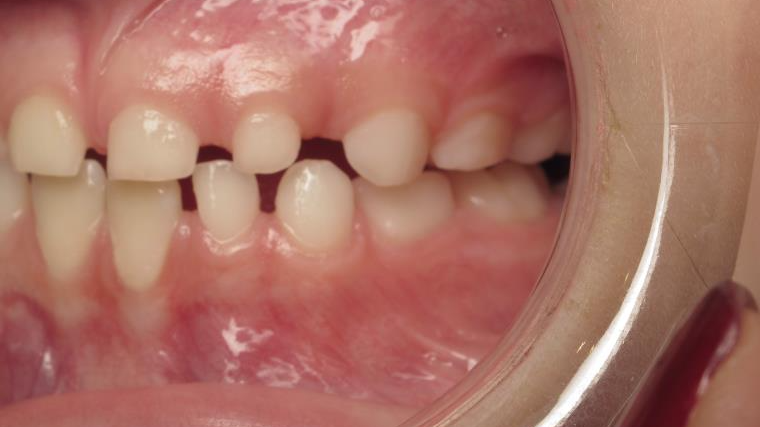

appareillage mobile pendant 35 mois

bilan début et en cours de traitement